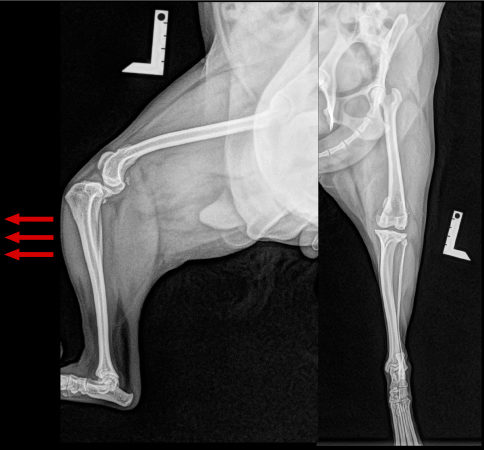

<レントゲン所見>

前十字靭帯断裂により、脛骨が前方変位しています。